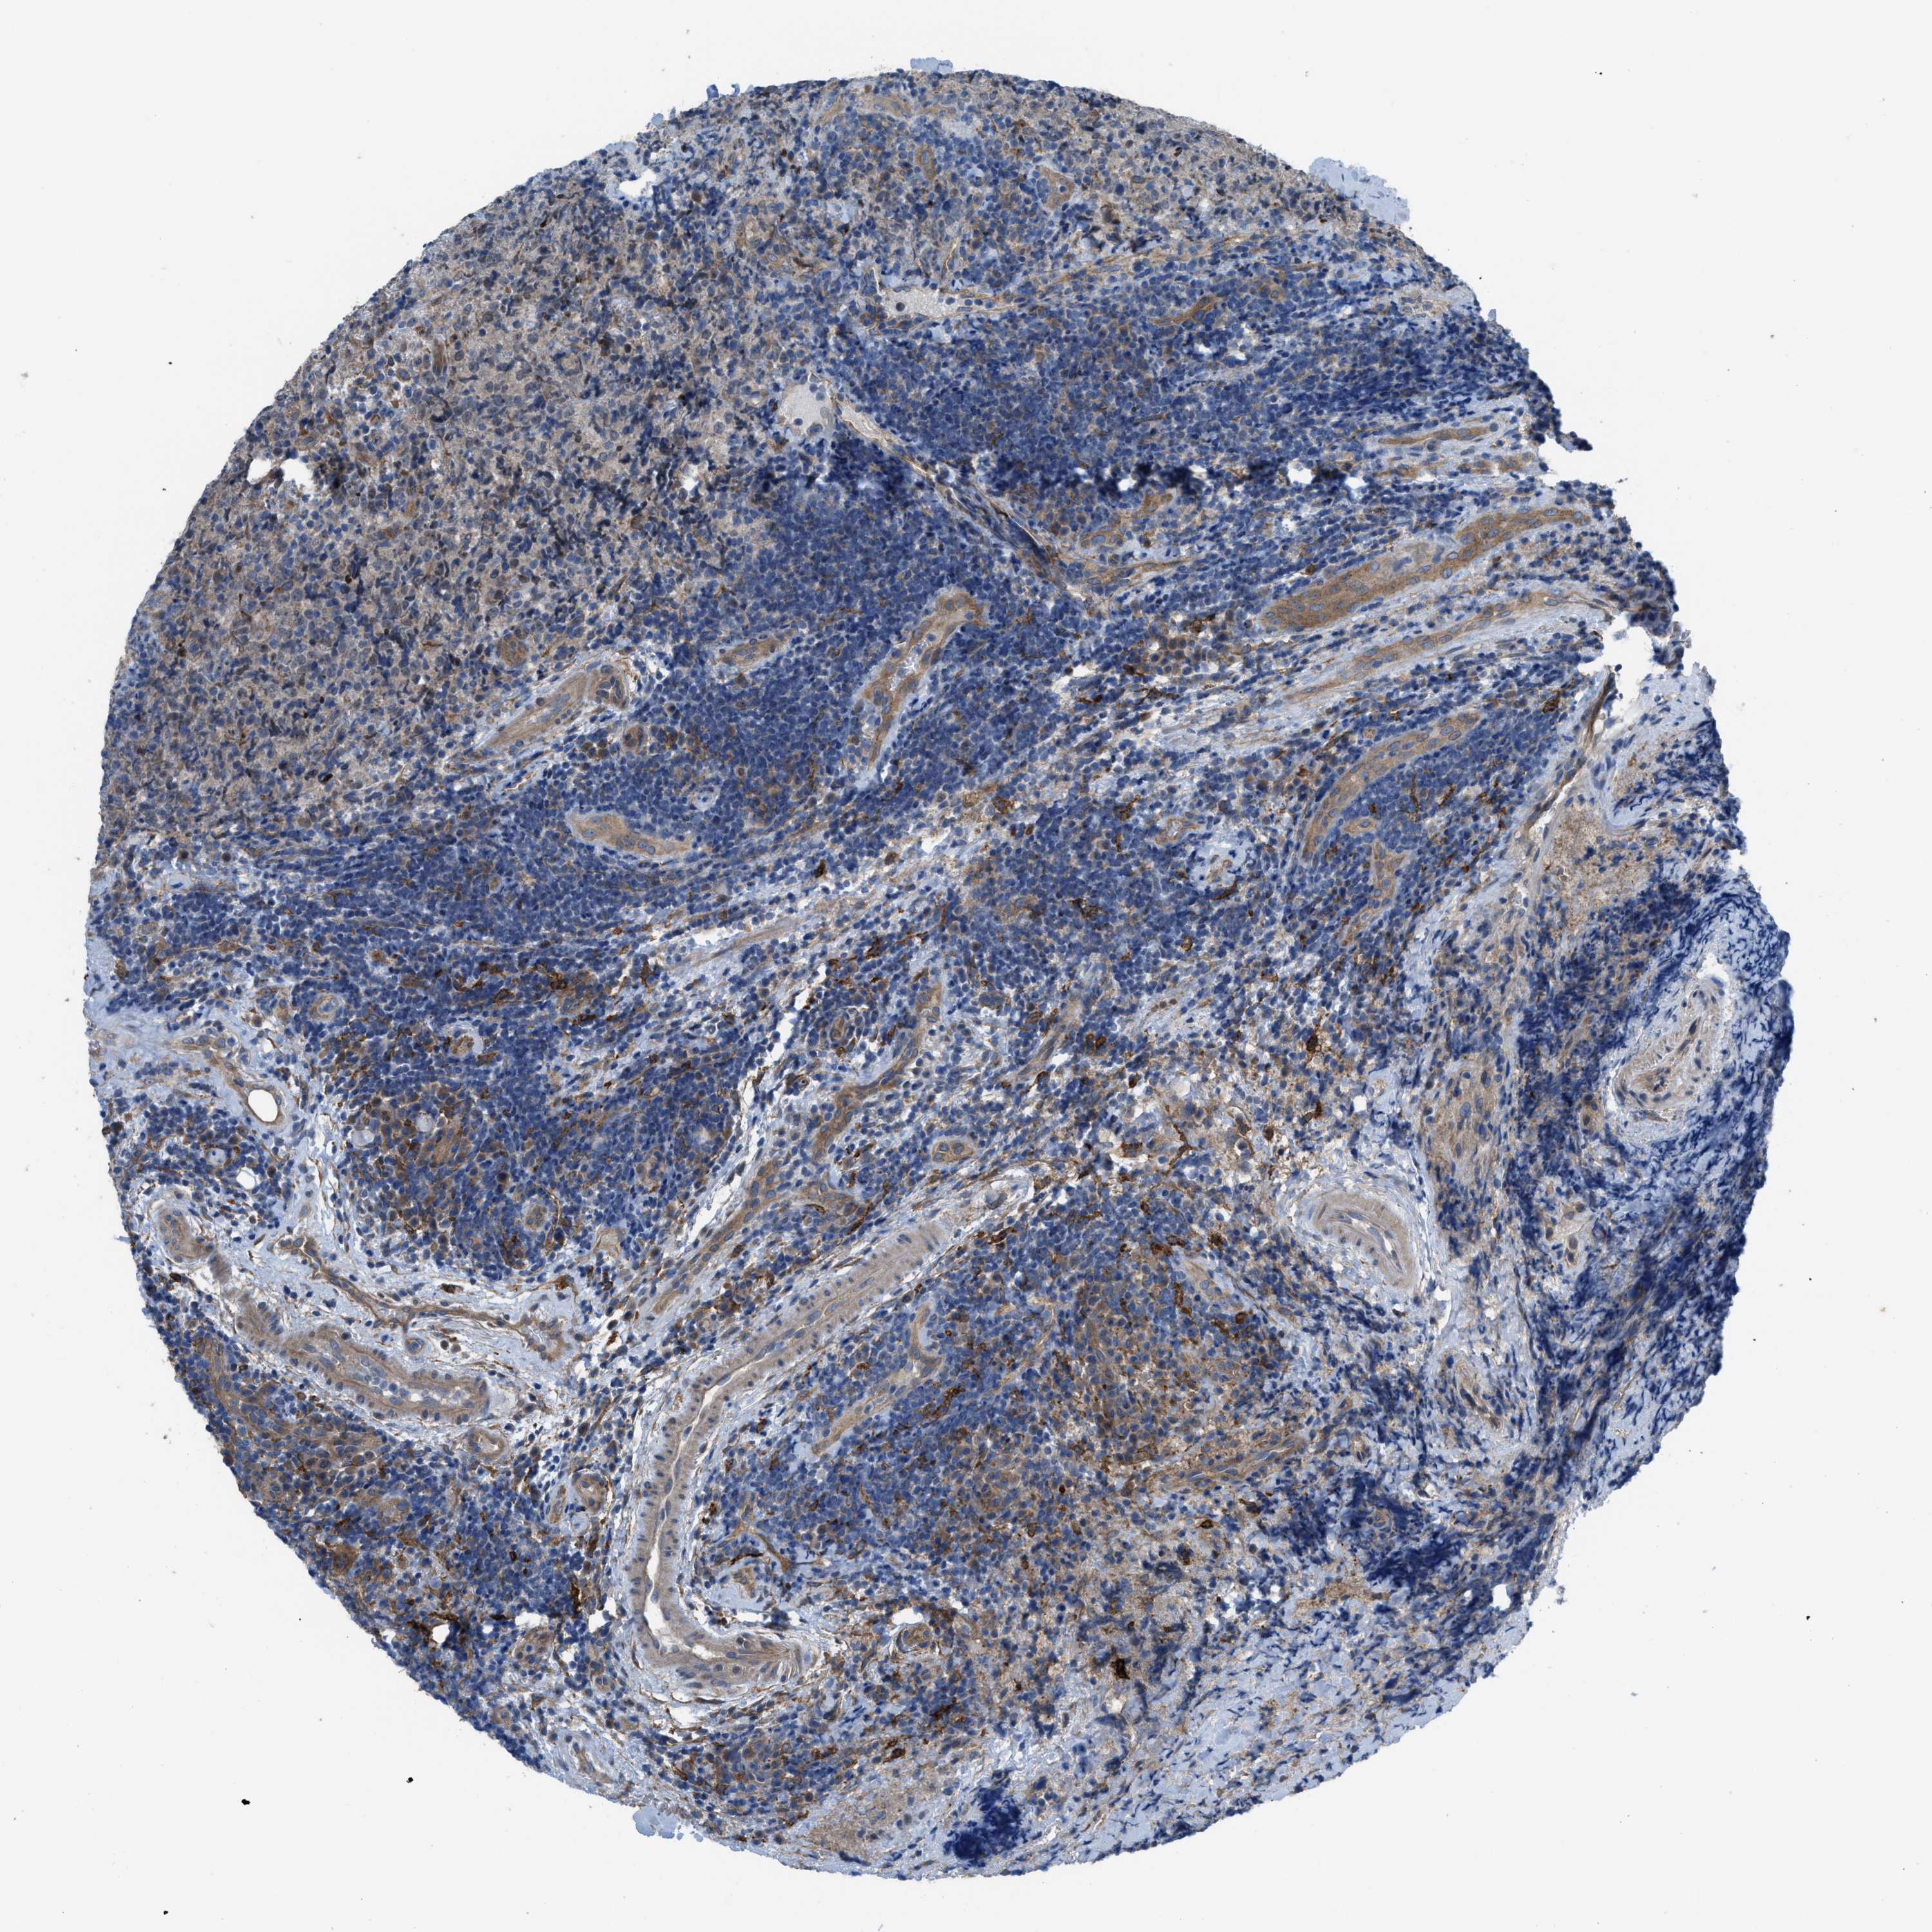

CANCER LYMPHOMA Show tissue menu

LYMPHOMA - Protein expressioni

A mouse-over function shows sample information and annotation data. Click on an image to view it in a full screen mode. Samples can be filtered based on level of antibody staining by selecting one or several of the following categories: high, medium, low and not detected. The assay and annotation is described here.

Each image is clickable and will lead to virtual microscopy that enables deeper exploration of all samples and also displays staining intensity scores, fraction scores and subcellular localization as well as patient and tissue information for each sample.

Malignant lymphoma, non-Hodgkin's type, High grade

Hodgkin's disease, NOS

Malignant lymphoma, non-Hodgkin's type, Low grade